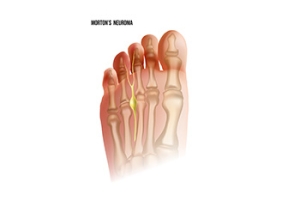

Symptoms and Causes of Morton’s Neuroma

Morton's neuroma is a painful condition that affects the ball of the foot, typically between the 3rd and 4th toes. It occurs when the tissue surrounding a nerve becomes thickened, causing irritation or compression. The exact cause of Morton's neuroma is not always clear, but factors like wearing tight or ill-fitting shoes, particularly high heels, can contribute by putting pressure on the ball of the foot. Other causes include repetitive stress or activities that involve high-impact movements, like running or jumping. Symptoms of Morton's neuroma include sharp, burning pain in the ball of the foot, tingling or numbness in the toes, and a feeling of something being stuck or bunched up in the shoe. These symptoms are often aggravated by walking or standing for long periods. If you have any of these symptoms, it is suggested that you contact a podiatrist who can successfully treat Morton’s neuroma.

Morton’s neuroma is a very uncomfortable condition to live with. If you think you have Morton’s neuroma, contact one of our podiatrists of Crystal Lake Foot & Ankle Center. Our doctors will attend to all of your foot care needs and answer any of your related questions.

Morton’s Neuroma

Morton's neuroma is a painful foot condition that commonly affects the areas between the second and third or third and fourth toe, although other areas of the foot are also susceptible. Morton’s neuroma is caused by an inflamed nerve in the foot that is being squeezed and aggravated by surrounding bones.

What Increases the Chances of Having Morton’s Neuroma?

- Ill-fitting high heels or shoes that add pressure to the toe or foot

- Jogging, running or any sport that involves constant impact to the foot

- Flat feet, bunions, and any other foot deformities

Morton’s neuroma is a very treatable condition. Orthotics and shoe inserts can often be used to alleviate the pain on the forefront of the feet. In more severe cases, corticosteroids can also be prescribed. In order to figure out the best treatment for your neuroma, it’s recommended to seek the care of a podiatrist who can diagnose your condition and provide different treatment options.

Morton's Neuroma

Morton's Neuroma, also called Intermetatarsal Neuroma or Plantar Neuroma, is a condition that affects the nerves of the feet, usually the area between the third and fourth toe. Neuroma refers to a benign growth that can occur in different parts of the body. Morton's Neuroma strictly affects the feet. This condition causes the tissue around the nerves that lead to the toes becoming thick, causing pain in the ball of the foot.

This condition can be caused by injury, pressure or irritation. Normally no lump will be felt, but instead burning pain in the ball of the foot will be experienced. Numbness and tingling may also occur. With the onset of this condition, a person may feel pain when tight or narrow shoes are worn. As the condition worsens, the pain may persist for days, or even weeks.

Persistent foot pain should always be a concern. The foot should be examined by a podiatrist if pain persists longer than a few days with no relief from changing shoes. The earlier the foot is examined and treated, the less chance there will be for surgical treatment.

There are some factors that can play a role in the development of Morton's Neuroma. These include wearing ill-fitting shoes that cause pressure to the toes, such as high heels. Also, high impact exercise may contribute to the cause of this condition. Morton’s Neuroma may also develop if the foot sustains an injury. Another cause includes walking abnormally due to bunions or flat feet. This causes excessive pressure and irritates the tissue. At times, people are affected for no determinable reason.

Podiatrists can alleviate the effects of this condition using a treatment plan to help decrease the pain and heal the foot tissue. Depending upon the severity of the Morton's Neuroma, the treatment plan can vary. For cases that are mild to moderate, treatments may include applying padding to the arch to relieve pressure from the nerve and reduce compression while walking. Ice packs can also help reduce swelling. The podiatrist may also create a custom orthotic device to support the foot and reduce compression and pressure on the affected nerve. The doctor will probably advise against partaking in activities that cause constant pressure on the affected area. They may provide wider shoes to ease the pressure from the toes. If these treatments do not relieve the symptoms of this condition, the doctor may use injection therapy.

Surgical treatment may be recommended by the podiatrist if all other treatments fail to provide relief. Normally, the podiatric surgeon will decide on either a surgical procedure that involves removal of the affected nerve or will choose surgery to release the nerve. After examination, the surgeon will decide on the best approach to treat the problem.

Recovery varies according to the type of surgical procedure. The patient will also be instructed on the best shoe wear to prevent the return of this condition, along with changes to workout routines, if this was a cause. Preventative measures are important in ensuring the condition does not return.